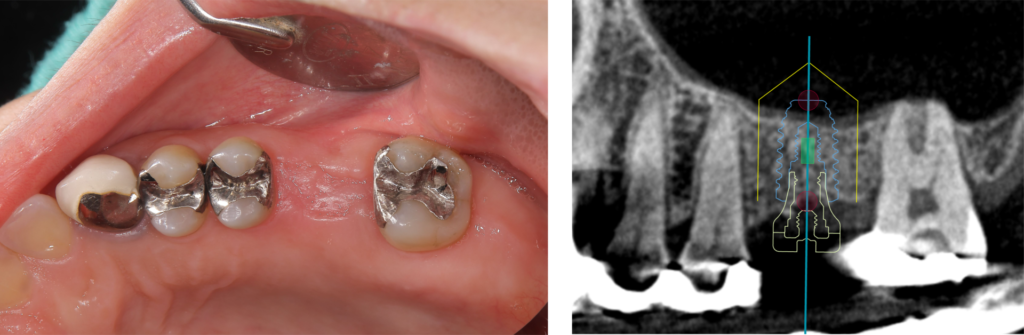

左図:骨の高さを増やしてインプラントを埋め込みました(サイナスリフト クレスタルアプローチ)

右図:治療前の予想インプラント位置(現存する骨に対して、インプラント先端が上顎洞に突き出ています)

図のように、骨の高さを増やすことによりインプラントが骨の中におさまっています